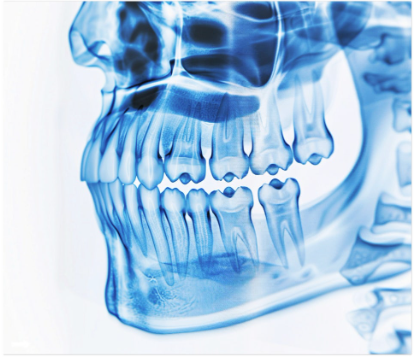

턱관절은 우리가 말을 하거나 음식을 씹을 때 반복적으로 사용하는 복잡한 구조의 관절입니다.

한의학에서는 턱관절 증상을 단순히 턱 자체의 문제로 보지 않습니다.

몸 전체의 균형과 연결하여 바라보는 것이 특징인데요.

✔️턱의 불균형이 경추나 어깨, 골반에 영향을 주거나 그 반대의 경우도 있을 수 있기 때문입니다.

그래서 턱관절뿐 아니라 머리, 목, 어깨, 골반까지 전체적인 체형을 함께 진단합니다.